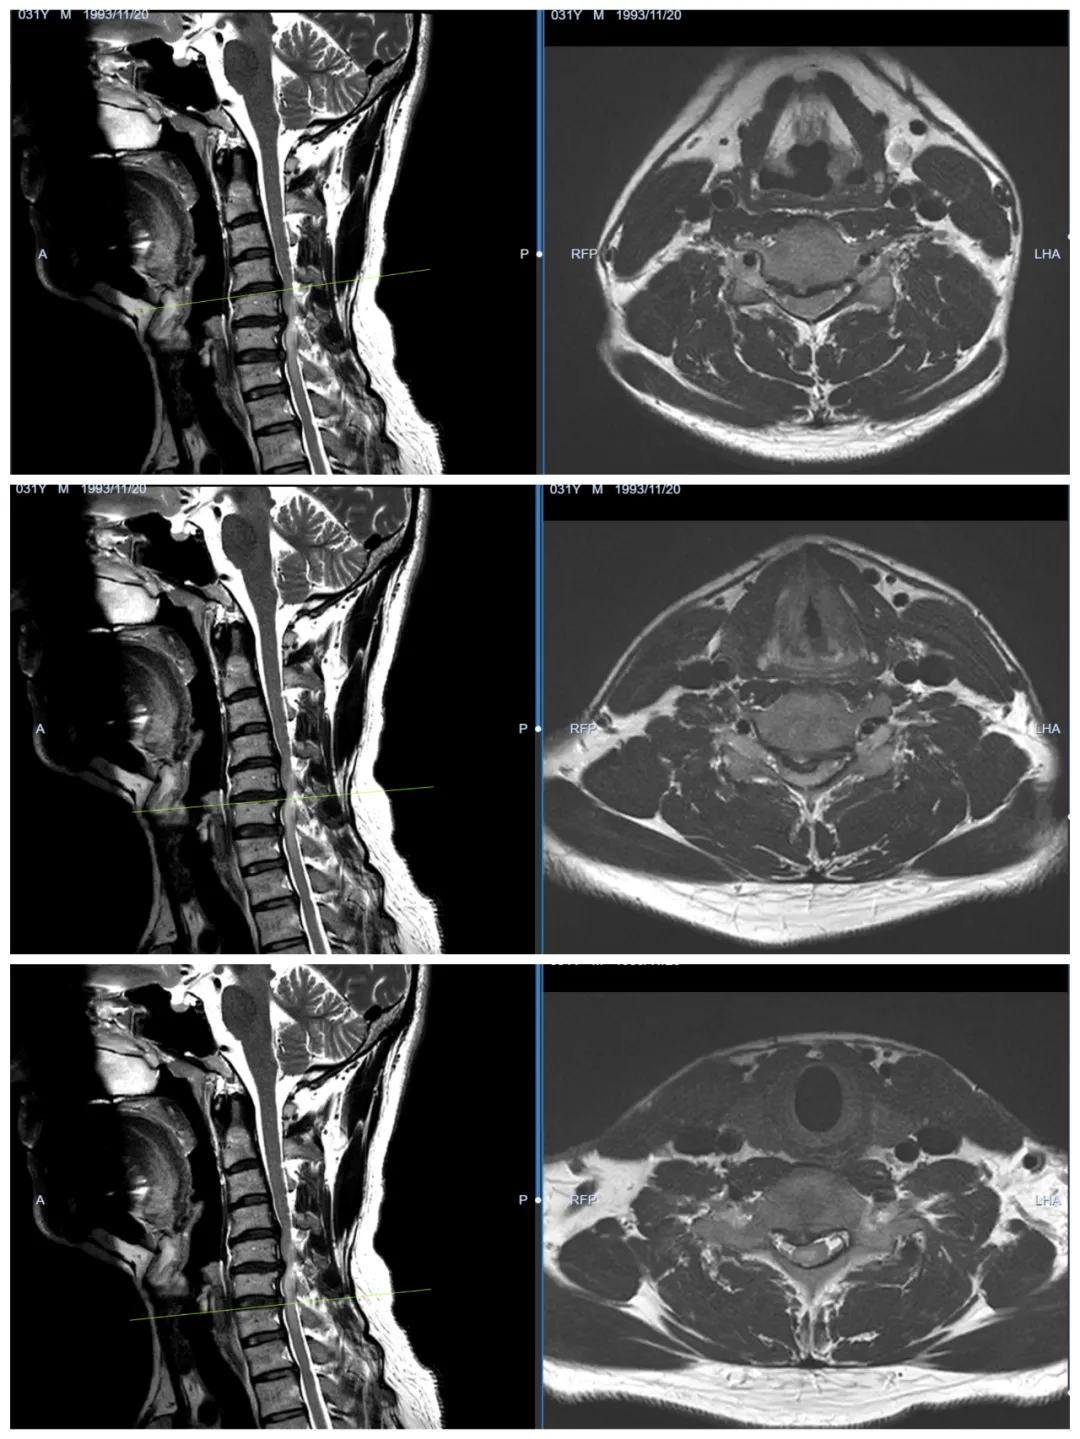

颈椎核磁结果显示,许先生的颈4-5、颈5-6和颈6-7的三节段椎间盘突出严重,且髓核向椎管内脱出,颈部脊髓明显受压,同时合并颈髓髓内缺血灶,呈现提示预后不良的“蛇眼征”(图1所示),需要尽快手术治疗。

图1,颈椎核磁:颈4-5、颈5-6及颈6-7三节段椎间盘突出,颈髓明显受压;同时合并颈髓髓内缺血灶,呈现提示预后不良的“蛇眼征”。